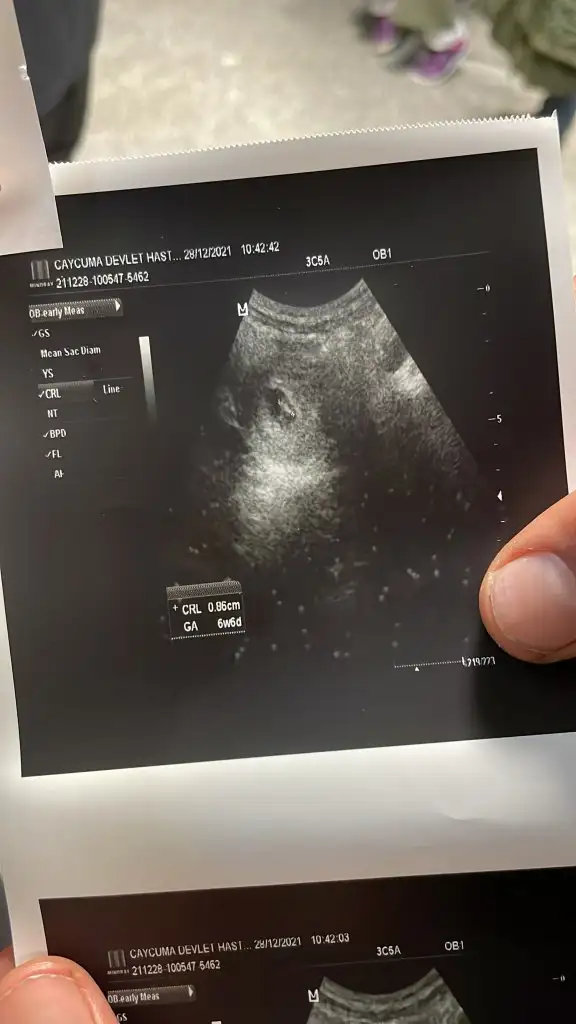

şuan için tek kese dedi nir dahaki kontrolde detaylı bakalım dedi 6+6 crl0,86 cıktı nasıl sizce

• 60A91D8F-08F9-41BE-BD26-D05D74F67EA5.webp